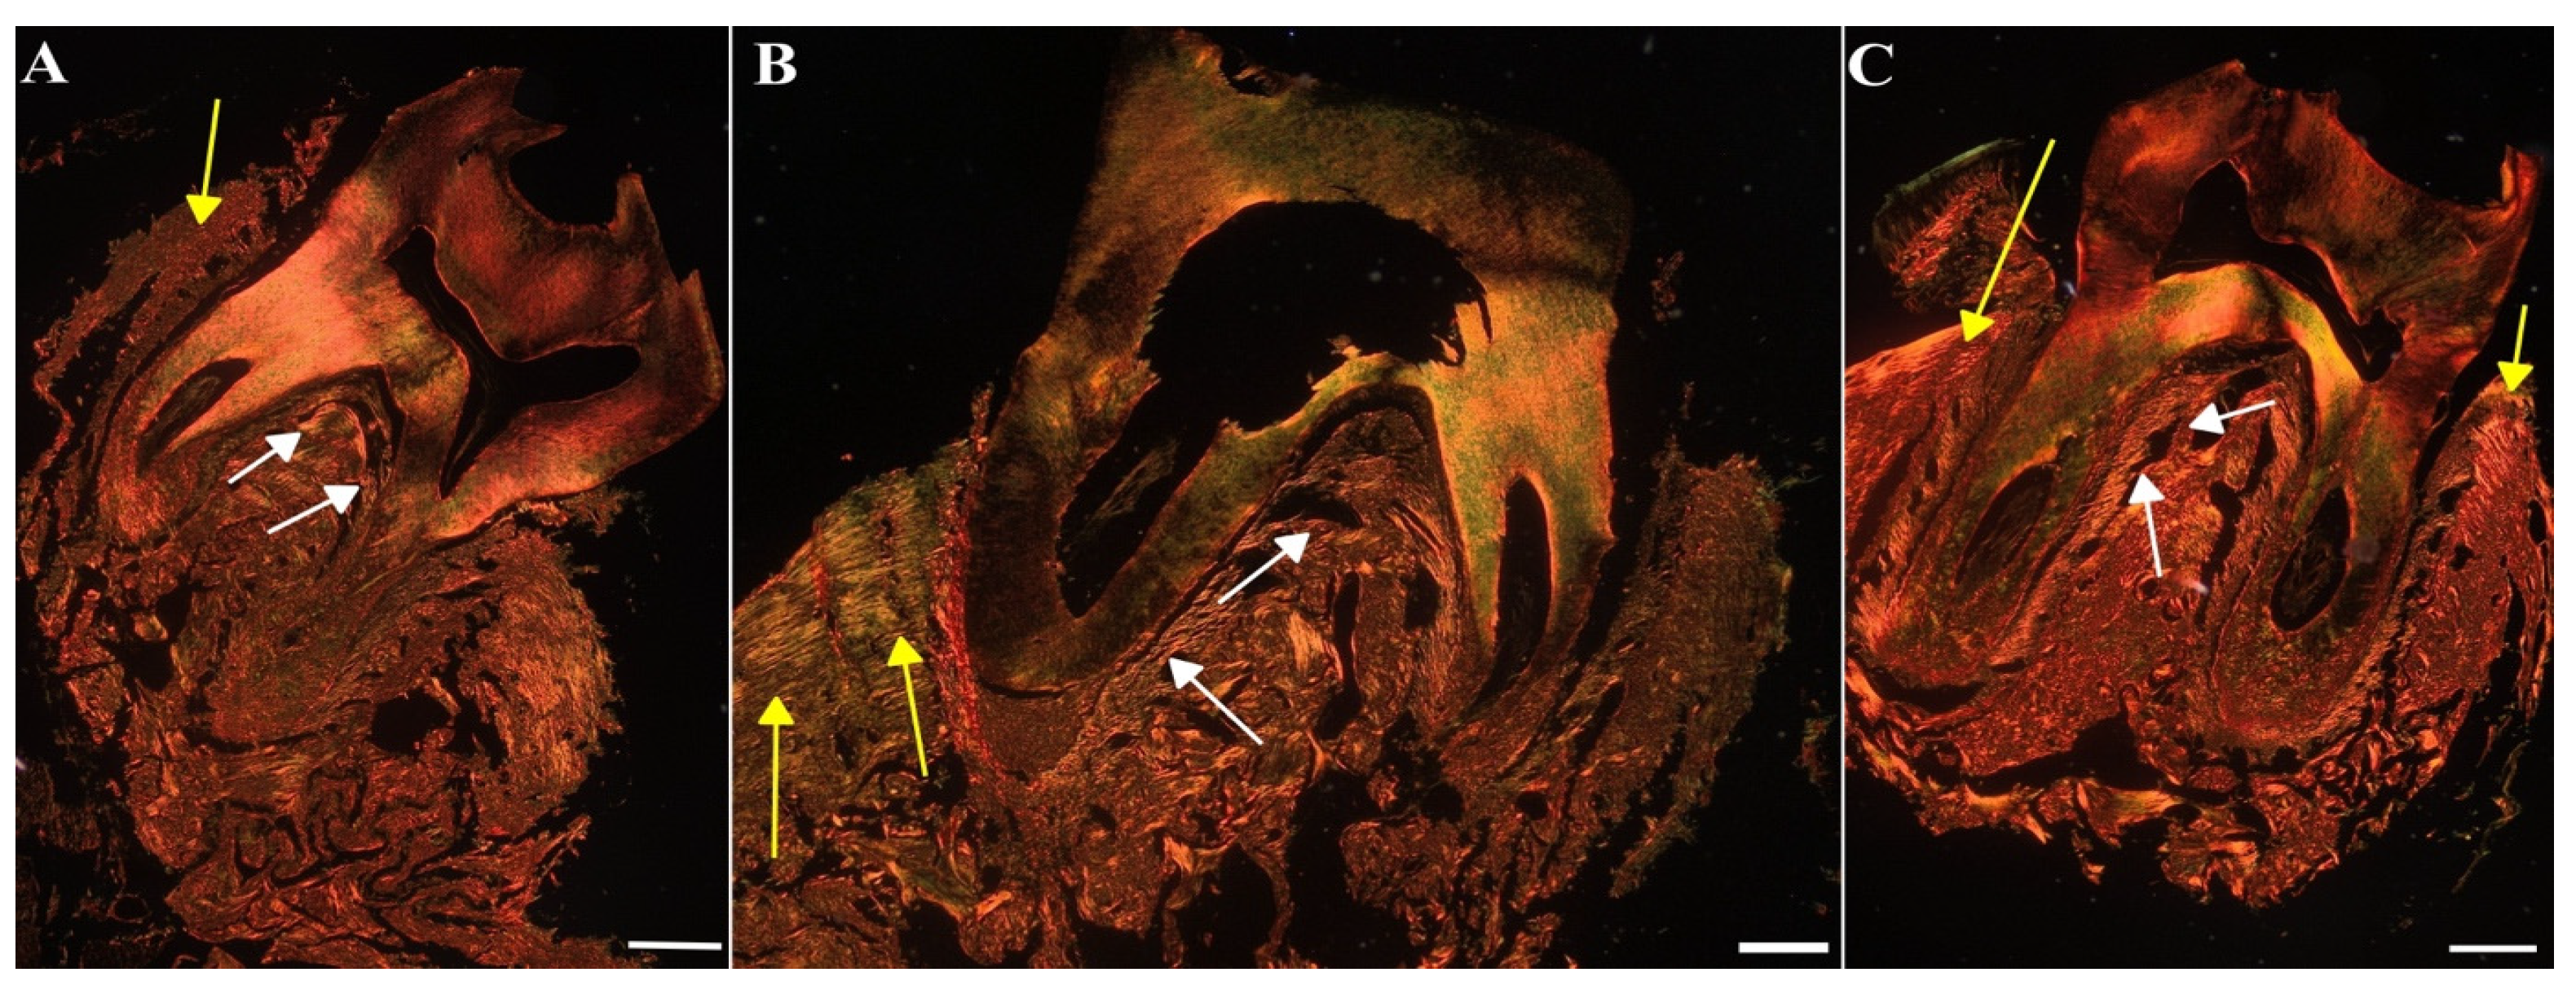

To assess the impact of MIN-T on the bone structure changes during periodontitis, immunohistochemical analysis of rat jawbone was conducted. Picrosirius red (PSR) staining was used to distinguish young and maturated collagen fibres in both compact and trabecular bone (indicated by yellow and white arrows, respectively, in Figure 11).

Another staining using toluidine blue was used to assess the microarchitecture of the trabecular bone and calculate the BV/TV parameter, which quantifies trabecular bone volume. Again, in the figure the compact and trabecular bone are clearly visible (indicated by yellow and white arrows, respectively, in Figure 12).

Significant differences (p < 0.05) were observed between the groups (Table S2): control (CG), untreated periodontitis (PG), and periodontitis pretreated with MIN-T (PG+MIN-T). Post-treatment, the trabecular bone volume (BV/TV) was slightly reduced in the treated group (PG+MIN-T), while it remained similar in both the control (CG) and untreated periodontitis (PG) groups. Additionally, there was a significant (Table S2) increase in trabecular separation (Tb.Sp) in the maxillary bone of the treated group (PG+MIN-T) compared to the control (CG) and untreated (PG) groups. This increase may indicate a potential weakening of the trabecular bone’s microarchitecture in the individuals who received the drug. Other parameters, such as trabecular number (Tb.N) and trabecular thickness (Tb.Th), showed no treatment effects on the microarchitecture of the trabecular bone (Table S2). For the trabecular bone, coarse collagen bundles were more prevalent in both the control group (CG) and the treated group (PG+MIN-T) compared to the infected, untreated group (PG) (Table S3), where bone tissue structure appeared significantly weakened. Because the Tb.Sp parameter is only one out of several indicators describing the microarchitecture of the trabecular bone and other parameters like Tb.Th and Tb.N are not affected, a significant deterioration in bone structure can be denied at this stage of investigation.

The ratio of fine-fibrous young to coarse-fibrous maturated collagen (Y/Mcompact) in the maxillary compact bone was significantly (p < 0.05) lower in the treatment group (PG+MIN-T) than in both the control (CG) and untreated (PG) groups (Table S3). This suggests that the local administration of the minocycline formulation may have induced the synthesis of new collagen. Furthermore, the proportion of maturated coarse-fibrous collagen (%Mcompact) in the compact bone of the maxilla was higher in both the treated (PG+MIN-T) and untreated (PG) groups compared to the control group (CG) (Table S3), indicating a compromised bone structure in the area due to the infection with P. gingivalis.

Interestingly, in the PG+MIN-T group, the size of the intertrabecular spaces in the maxillary bone was significantly larger, compared to the control (CG) and non-treated (PG) groups. This may suggest a potential weakening of the trabecular bone microarchitecture as a first impression. The trabecular space (Tb.Sp) parameter is thereby only one of several indicators describing the microarchitecture of the trabecular bone. If an increase in Tb.Sp would be associated with a thinning of the beads (a decrease in trabecular thickness, Tb.Th) and a decrease in the number of bone beads (Tb.N.), then this would indicate a significant deterioration in bone structure. The study results clearly show that MIN-T is not affecting other parameters, such as Tb.N and Tb.Th. Following this information, the application of MIN-T seems not to have a significant negative influence on the microarchitecture of the trabecular bone. For a complete picture, bone strength tests will be a valuable source of information. Therefore, it is planned to expand the analyses to include such techniques in future studies. Additionally, the non-treated periodontitis group PG exhibited a decrease in the percentage of maturated coarse-fibrous collagen and a significant increase in the percentage of fine-fibrous collagen as well as the ratio of young fine-fibrous to maturated coarse-fibrous collagen bundles within the trabecular bone of the maxilla, compared to both control and treated animals PG+MIN-T. This might indicate disturbances in the collagen network of the trabecular bone in the jaws of infected rats, suggesting that drug administration positively affects bone turnover by eradicating bacteria, and indicating induction of new collagen synthesis following an anti-infective treatment.

Moreover, the percentage of coarse-fibrous collagen (%Mcompact) in the compact bone of the maxilla was significantly increased in both untreated (PG) and treated (PG+MIN-T) animals compared to controls (CG), signaling a compromised bone structure in this area of the maxilla due to an infection with P. gingivalis. In summary, while the administration of MIN-T does not enhance the microarchitecture of the trabecular bone in the maxilla, it also does not significantly deteriorate it. Furthermore, drug administration does not significantly impact collagen synthesis, which could potentially increase the stability of collagen fibres and improve the condition of the trabecular bone.

4.6.2. Bone Density